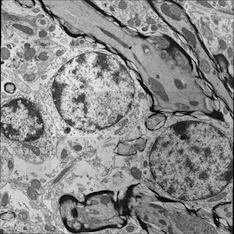

For image analogies based image registration, I have corresponding TEM/Confocal Microscopic image pairs of mouse brains with corresponding regions highlighted by a box. Using the correlative microscopy technique on the mouse brain, I want to localize specific brain regions associated with Pelizaeus-Merzbacher Disease (PMD) and do quantitative assessment of hypomyelination and demyelination in mice. PMD is one of a group of genetic disorders characterized by progressive degeneration of the white matter of the brain affecting the myelin sheath, the fatty covering that acts as an insulator on nerve fibers in the central nervous system.

The confocal microscopy images are multichannel color images in our test dataset. The blue channel is based on the blue stain DAPI (a fluorescent stain) which stains the DNA of the cell nucleus and corresponds to dark regions within the nuclei in the TEM. The green channel is based on the stains of the myelin sheats, visible as dark black layers covering the neurons in the TEM images. The red channel is not explicitly stained for and is caused by the auto-fluorescent effect of lipofuscin. The confocal image with RGB channels and its corresponding TEM image are shown in Fig. 5.

(f) TEM image

Figure 5: Example of Confocal image with RGB channels and TEM image